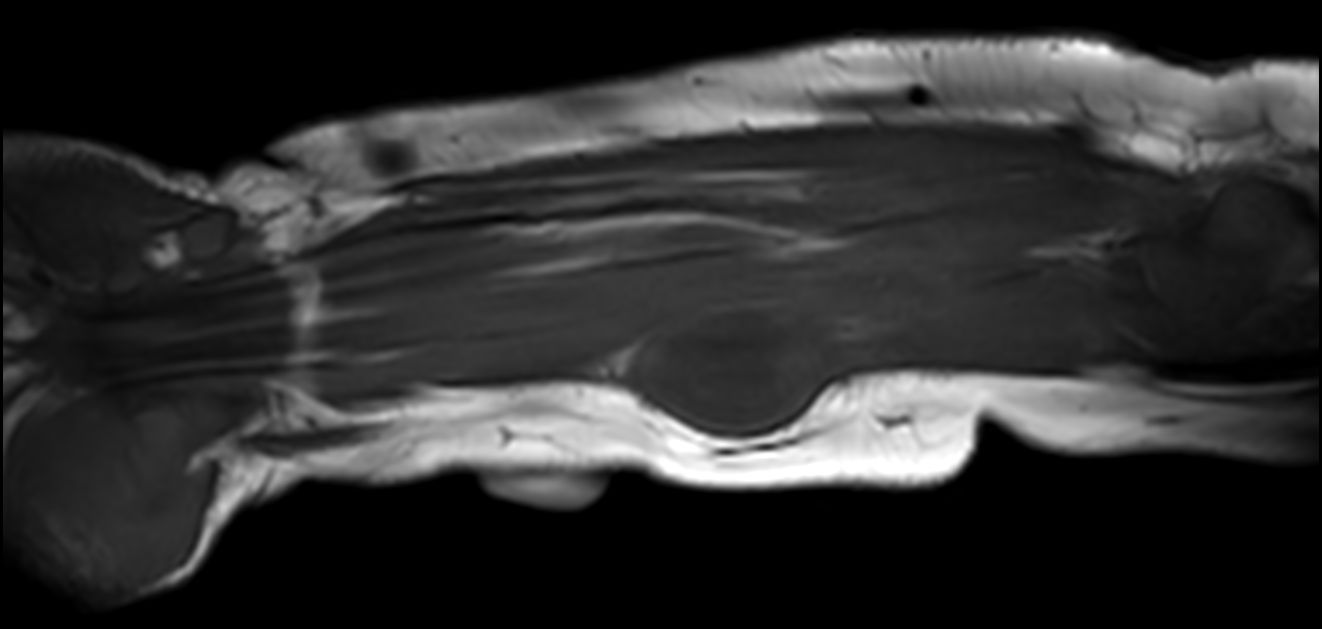

Pediatric forearm with lesion

Pediatric patient with a lesion in the forearm. mDIXON XD provides uniform fat-free imaging and allows for multiple image types in one single scan. Integration of Compressed SENSE acceleration technique enables speeding up of the entire exam.

Sagittal T2w mDIXON XD (In Phase)Compressed SENSE